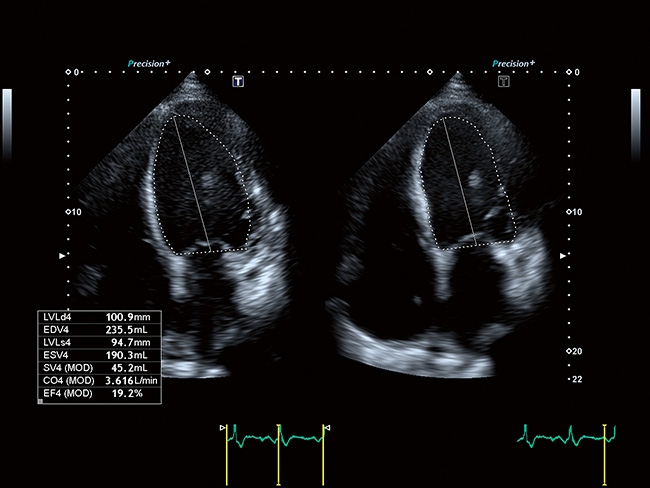

Aplio a550 может работать с линейным матричным датчиком и поддерживает новейшие монокристаллические датчики. Также Aplio a550 поддерживает большое количество дополнительных опций, таких как - SMI, Компрессионная эластография, Эластография сдвижной волны, Smart Fusion, исследования с использованием контраста (CEUS), 3D реконструкции в реальном времени (4D), функции автоматической оценки подвижности миокарда и фракции выброса.

Отличная цветопередача с высокой детализацией и четкостью изображения. Устройство подходит для профессионального использования в частных кабинетах и крупных медицинских центрах. Комплектация сканера применима для самых разных исследований. Широкий диапазон прикладного клинического программного обеспечения высокоэффективен для общих исследований, сердечно-сосудистых, гинекологических, ортопедических, урологических.

Общая визуализация, Гинекология и акушерство, УЗИ для кардиологии

Кардиология:

Да